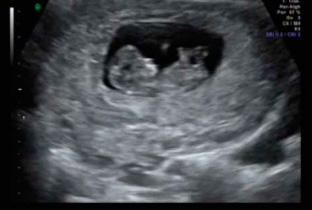

Ultrassonografia

Exame de diagnóstico por imagem que aproveita o eco produzido pelo som para capturar e enxergar, em tempo real, estruturas e órgãos do corpo. Utiliza ondas sonoras de alta frequência para produzir imagens do interior do corpo, sem o uso de radiação ionizante (Raios - x). Como as imagens são adquiridas em "tempo real", podem mostrar além das características morfológicas das estruturas, o movimento dos orgãos internos do corpo e o sangue correndo através dos vasos.